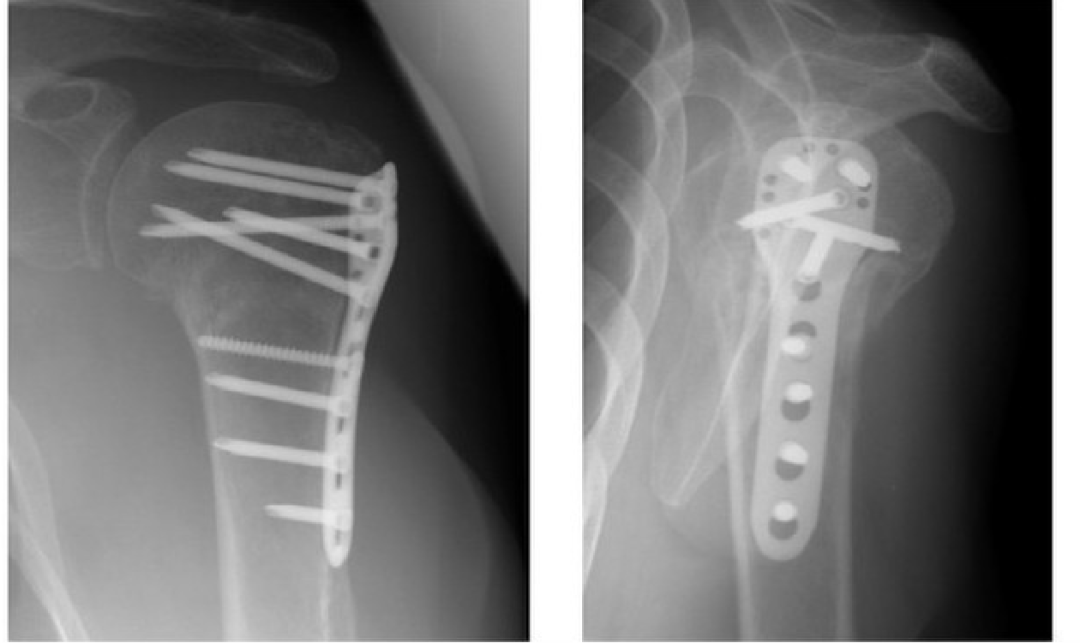

锁定钢板内固定肱骨近端锁定钢板:目前是肱骨近端骨折有效的固定方式之一。其外形与肱骨近端外侧面的解剖形态相吻合,即使骨质疏松症的患者,也可以可靠地固定肱骨头及相关的骨碎块。这主要因为螺钉与钢板锁定以后形成角稳定装置,并且螺钉在肱骨头内呈三维分布。肱骨近端锁定钢板与肱骨近端外侧面的解剖形态相匹配,作为一种内固定支架,通过角稳定装置可维持骨折的解剖复位。肱骨头内四枚锁定螺钉的分布方向各异,构成一个三维立体结构。钢板上另设计有小孔,通过这些小孔可用缝线或钢丝进行固定。对于粉碎性骨折,这一方法可将大结节和小结节骨折块聚拢,重新固定,并可对抗肩袖各肌肉对骨折块的牵拉。

放置肱骨近端锁定钢板时,可借助瞄准装置确定理想的位置:距离肱骨大结节上缘5-8mm并位于结节间沟外侧2-4mm,确保钢板与肱二头肌长头腱之间有足够的缓冲区。置入钢板时如果必要的话可在三角肌止点处做适当的剥离。应用影像增强器确认钢板位置和骨折的复位是否满意。为了避免撞击,必须注意不要将钢板放置得太靠近段。第一枚螺钉通常为3.5mm皮质骨螺钉,应用标准操作规程置入靠近骨折端的螺孔内。这一螺钉可对抗胸大肌对肱骨干骨折块的牵拉。拧紧螺钉时,必须留心,确保钢板的远端部分位于肱骨干的正中。

应用钻头导向器,在肱骨头内置入角稳定螺钉(锁定螺钉)。用2.8mm钻头钻孔后,测深,确定螺钉的长度,置入锁定螺钉。在骨干上最少要有2枚双皮质锁定螺钉,对于骨质疏松性骨折则至少要用3枚,以免螺钉松动拔出。

肱骨近端锁定钢板应放置在肱骨大结节顶端以远5-8mm处。缝线穿过钢板上的小孔打结固定,这样可以对抗肩袖的张力,进一步增加骨折固定的稳定性。

在直视下进行被动活动,检查固定的稳定性,然后在拍摄X线影像,特别需要注意的是复位的结果、钢板的位置、固定的稳定性以及螺钉的长度等。由于肱骨头内的螺钉方向各异,因此必须在影像增强器监视下旋转上臂确定每一枚螺钉的位置都准确无误,最后拍摄腋位X线影像。最后冲洗创口,逐层缝合。术后拍摄X线片记录骨折复位和内置物的位置